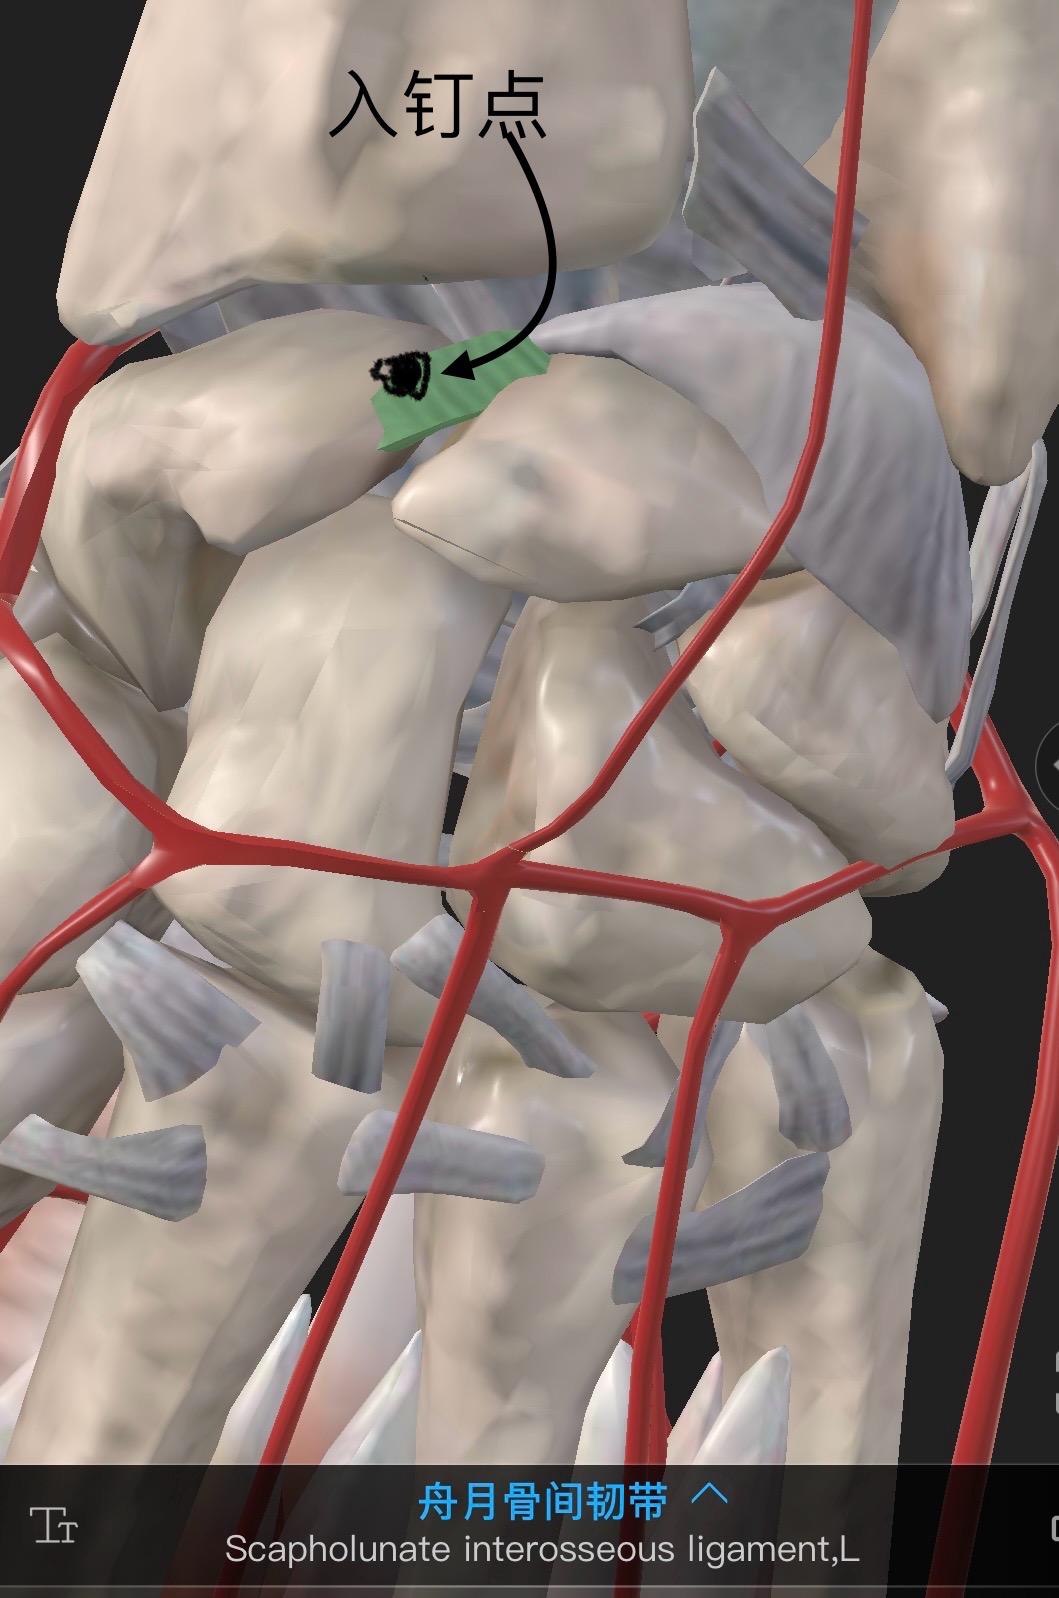

2)完全屈曲腕关节,充分显露舟骨近极,自近极尖端,沿舟骨中轴(向掌侧和桡侧方向,与外展拇指的方向一致)钻孔,置入Herbert钉,埋入关节软骨下。(注意:螺丝钉指向舟骨掌桡侧结节部)

3)适用于舟骨近侧1/3骨折,屈腕切开关节囊,看到舟骨近极和舟月联合。螺丝钉入点尽可能靠近舟月韧带,稍偏于拇指列掌侧。

逆行法入路空心钉自近端打入